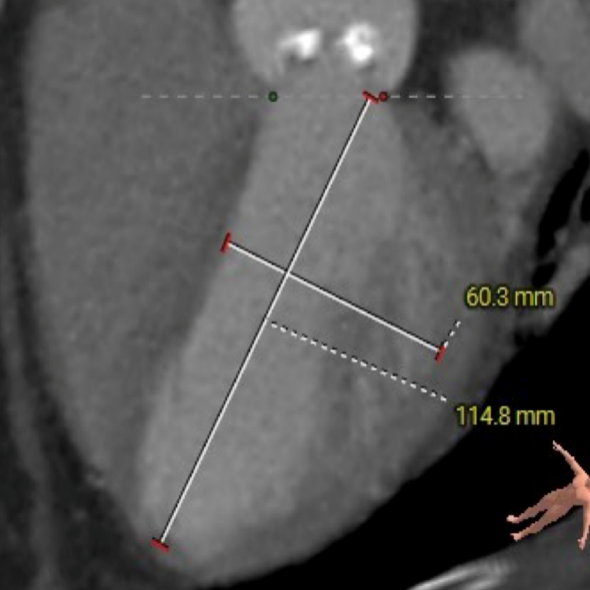

主动脉根部测量

ANNULUS

SOV DIAMETER

LVOT

STJ

ASCENDING AORTA

LEFT VENTRICLE

CT数据显示该患者为type1型主动脉瓣。

主动脉瓣瓣环周长75.2mm,平均周长径 23.9mm,SOV:34.7mm*33.8mm*32.9mm,瓣叶增厚,瓣上钙化分布不均,瓣环水平夹角58°。

冠脉高度测量

LEFT CORONARY

左冠开口高度14.0mm

RIGHT CORONARY

右冠开口高度13.1mm

钙化分布